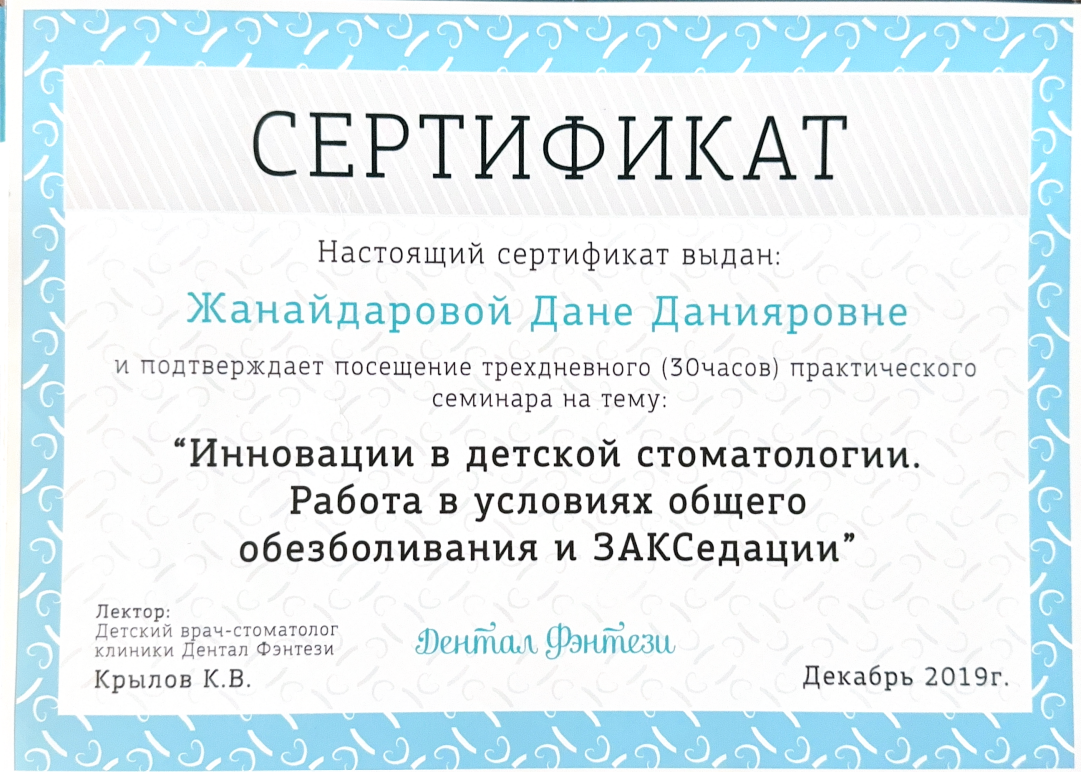

Регулярно совершенствует знания в стоматологии